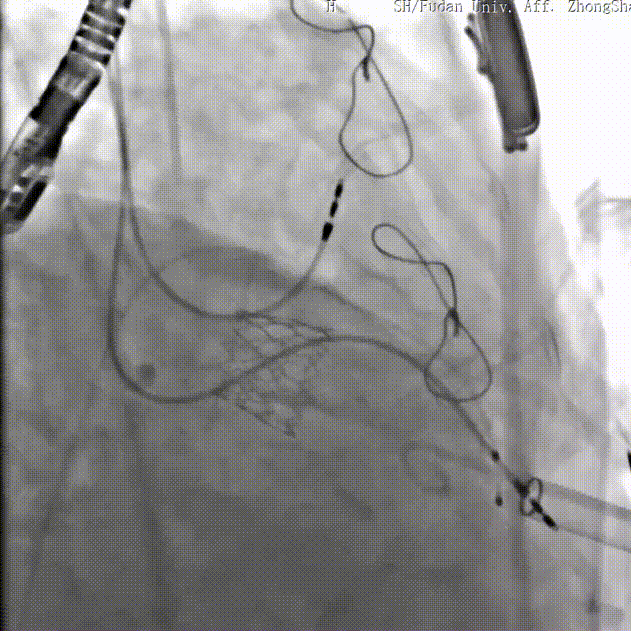

患者女性,73岁,既往二尖瓣位植入27# Epic猪瓣,超声提示二尖瓣人工瓣膜衰败伴重度关闭不全,瓣叶连枷。该患者还合并重度贫血、低白细胞、低血小板、多囊肝、多囊肾、永久起搏器植入术后、心功能NYHA III级、营养状况极差,术前STS评分12.1%,属于常规外科手术极高风险患者。术前经详尽影像学评估及病例讨论,考虑到患者既往经房间隔切开植入二尖瓣人工瓣膜,房间隔疤痕钙化严重增加穿刺手术风险,决定采用更安全的经心尖途径植入27号Renato球扩式瓣中瓣。

手术耗时约1小时,全程生命体征平稳,几乎无出血。瓣中瓣植入位置理想,功能表现出色:左房压自术前50/15/27mmHg降至21/11/15mmHg,二尖瓣平均流速自2.2m/s降至1.4m/s,二尖瓣平均跨瓣压差自6mmHg降至3mmHg。